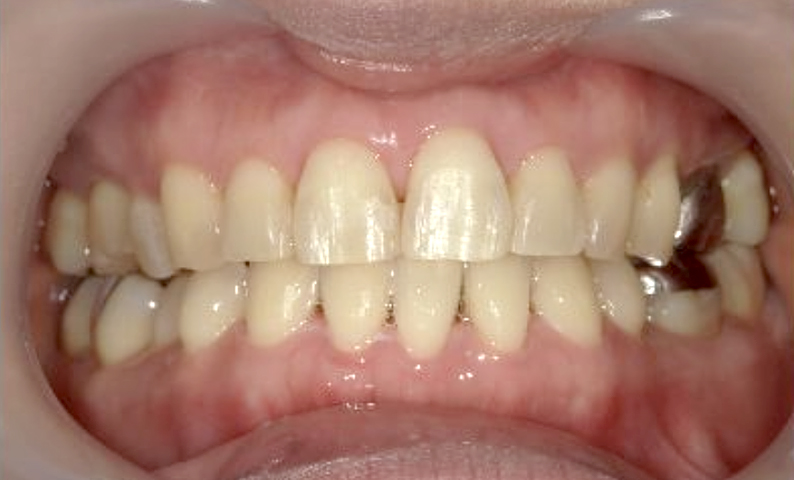

症例_030 上下顎の部分矯正

治療期間:12ヶ月金額:54万円+税女性八の字/V字型捻転歯前歯のガタガタ

| Before | After |